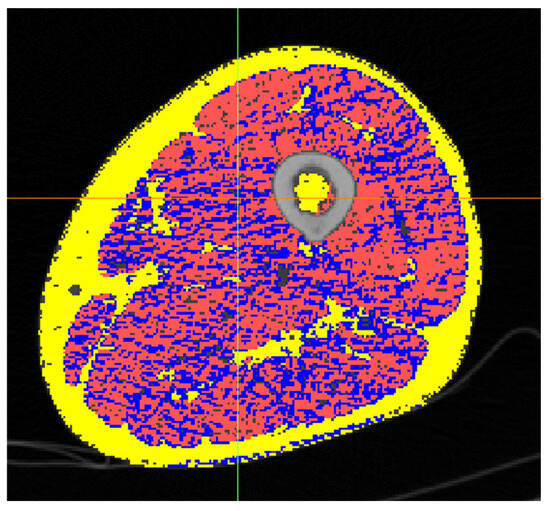

2.5. Quantitative Image Analysis

2.6. Results

2.6.2. Study B: Thigh Muscle Quality Compared to AGES-Reykjavik Population